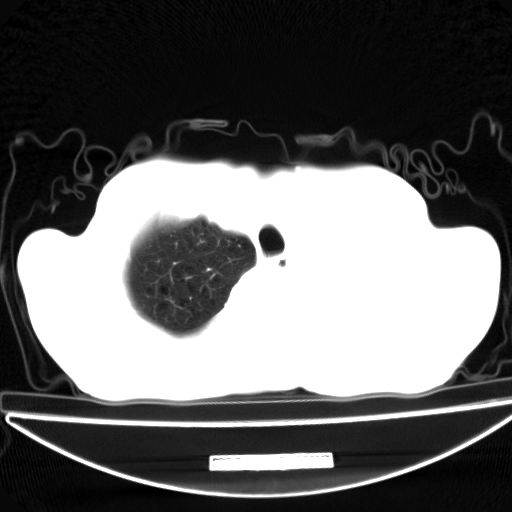

以下是引用杀毒软件在2009-4-28 17:58:00的发言:[br]考虑----左肺慢性肺脓肿形成继发上叶含气不良---抗炎后复查---待排肿瘤所致[br][br][本贴已被 杀毒软件 于 2009-4-28 18:01:26 修改过]